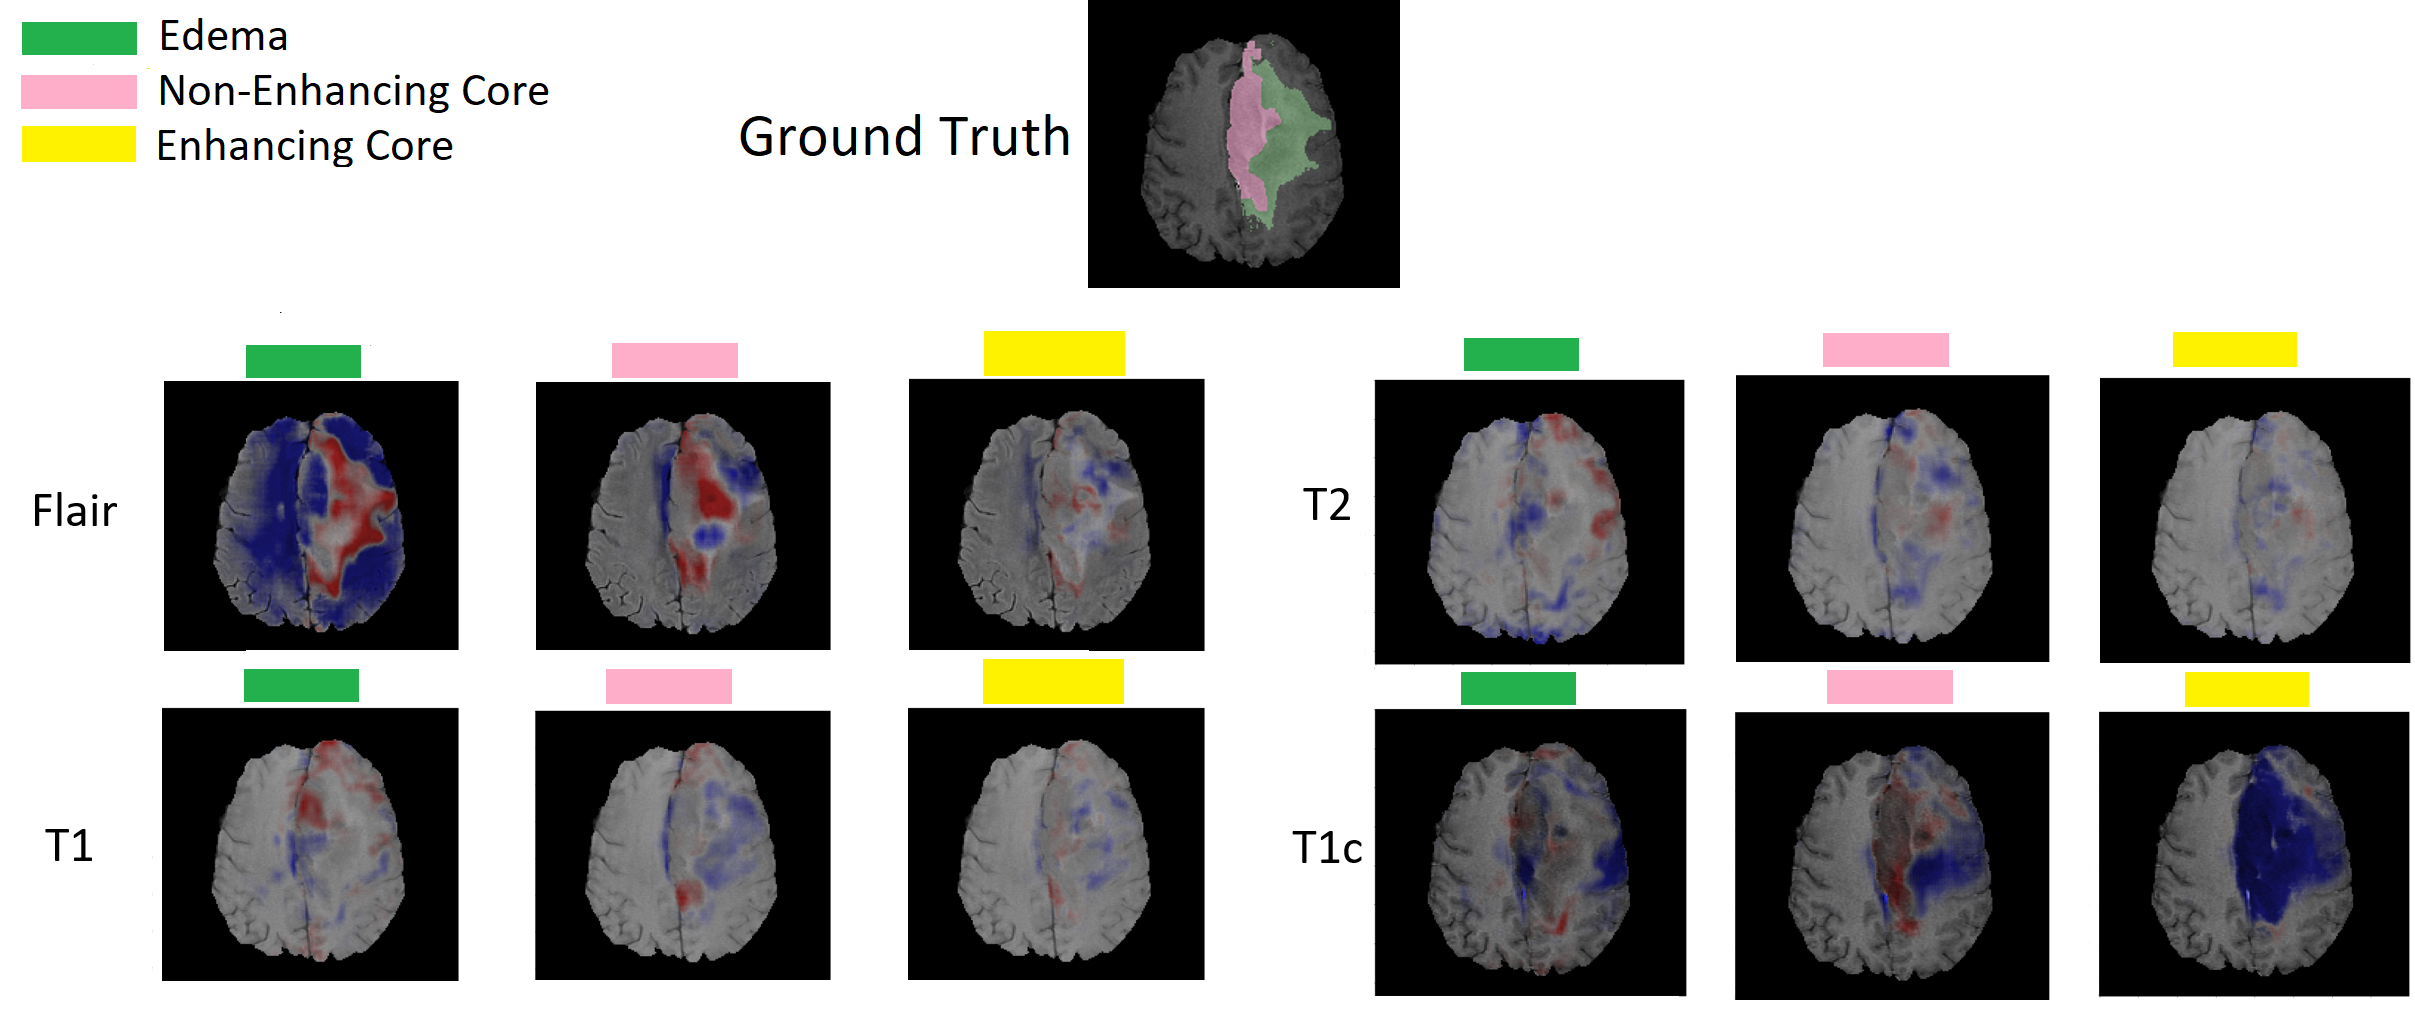

Finally, to provide interpretations on which our prediction is based, we generated relevance map by the method we described in Section 2.5. This helps us to understand the role of each individual channel on the estimation of whole tumor, tumor core and enhanced core. Our model has a surplus benefit of generating meaningful interpretations as our network broadly adapts to full channel and missing channel input.

Fig. 4 shows the contribution of each channel while predicting three types of tumors at pixel level. By weighting the prediction differences between inputting full channels and removing a specific channel, we visualize the influence of each channel to an individual segmentation label. Red color represents positive evidence, and blue color represents negative evidence from that channel to the segmentation label. We observed that, different channels contribute distinctly to different tumor types.

For example, Flair channel provides a strong positive evidence on the whole tumor regions and a negative evidence of the non-tumor regions. T2 channel refines the evidence across the boundary area. T1c channel provides supporting evidence both on tumor core and enhanced core area against the rest in the whole tumor area. T1 channel refines the evidence across the boundaries of tumor core area. In general, we trust the segmentation classifiers that could not only produce exact and distinct labels for each tumor type, but also provide reasonable explanations for its decisions.

We propose a brain tumor segmentation algorithm that is robust to missing modality. Our model is designed to recover the information from missing modality and is able to visualize the contribution of each channel. The comparisons between full and missing modality show the important roles of Flair and T1c on discrimination of whole tumor and tumor core, respectively. These findings are along well with the expert labeling routine [12].